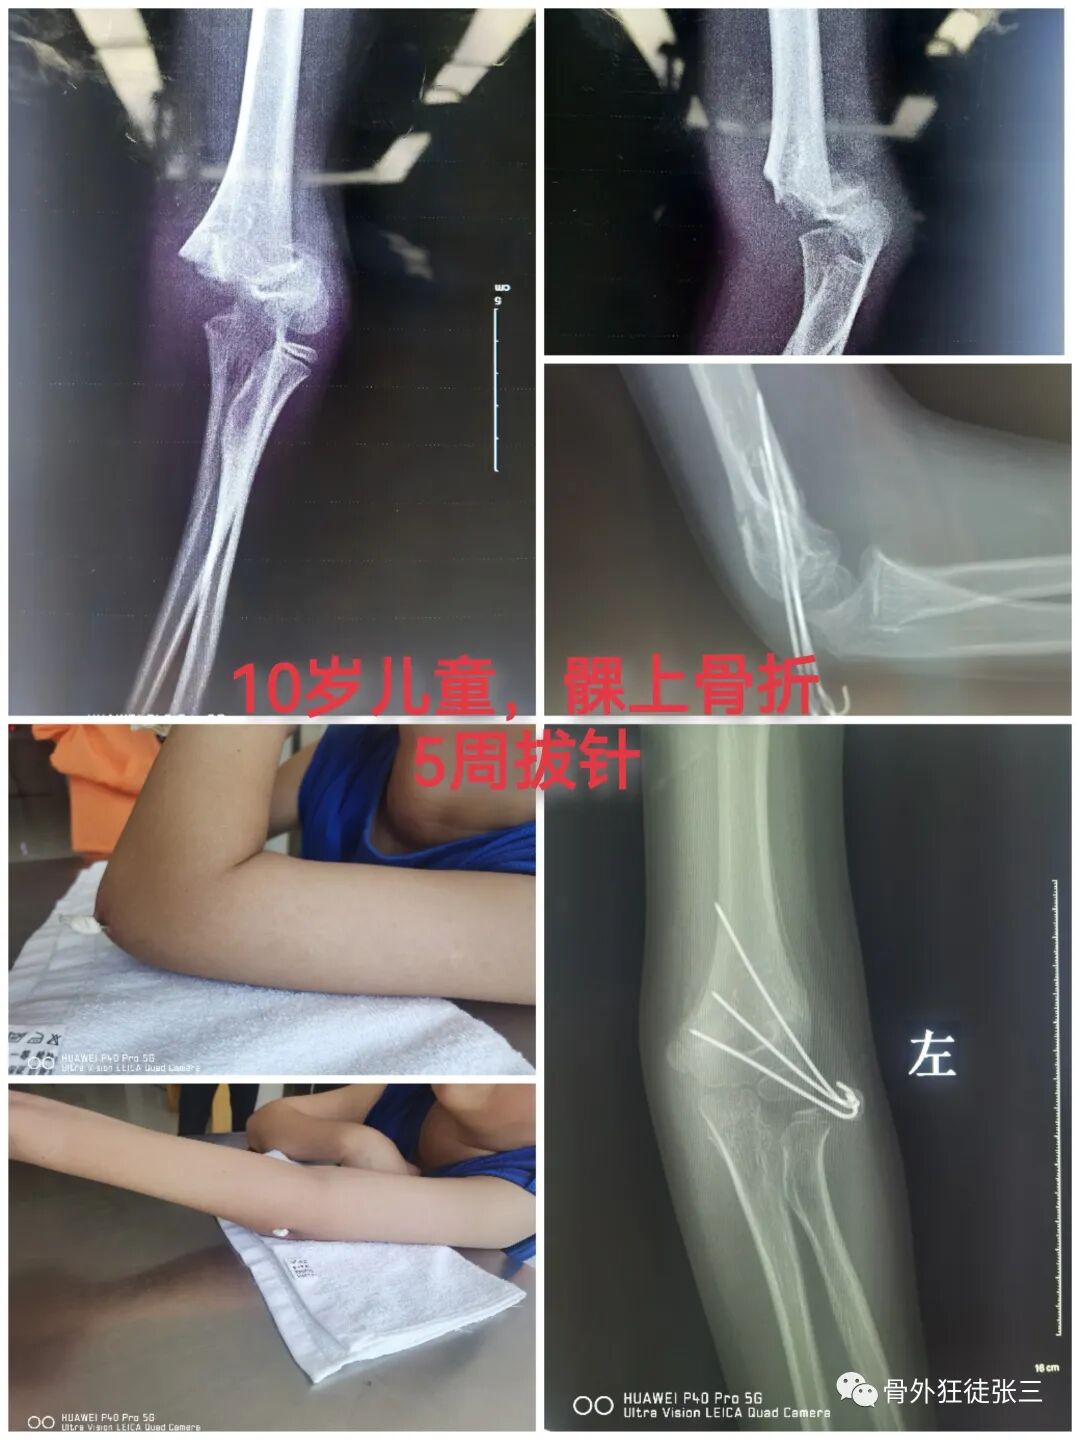

病例14,儿童髁上骨折零切开,桡侧三枚针发散固定

病例15,儿童髁上骨折零切开,